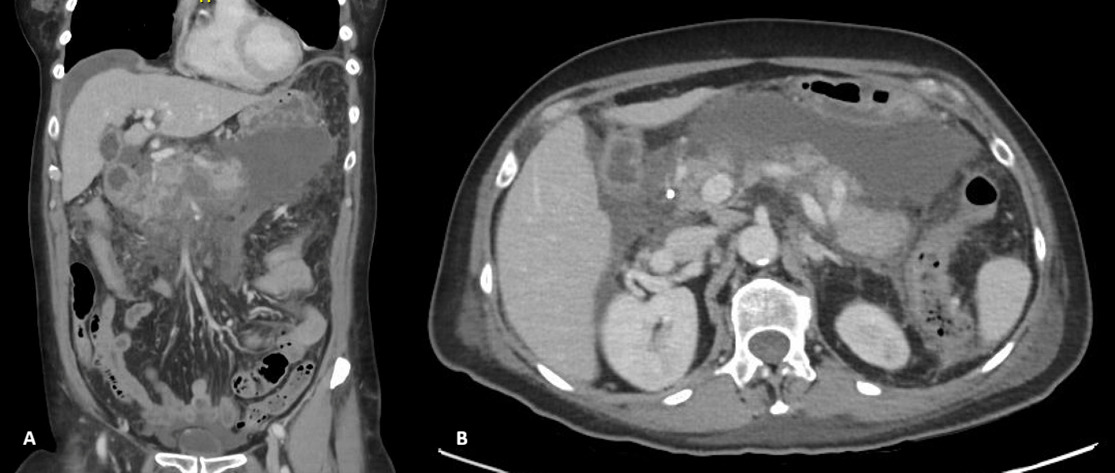

Ten days following initial presentation, the patient was referred for endoscopic drainage of the peripancreatic fluid collections. Endoscopic ultrasound-guided drainage was performed with insertion of a lumen-apposing metal stent (AXIOS) and an additional plastic stent into the largest collection. A repeat contrast-enhanced CT scan was recommended two weeks following stent placement to assess treatment response (figure 2).

On this interval CT imaging, the distal common hepatic artery (CHA) and the proximal left (LHA) and right hepatic arteries (RHA) were noted to be non-opacified, with soft tissue attenuation tracking along the expected course of these vessels. In the clinical context, these findings were most consistent with arterial thrombosis with associated vessel expansion or pseudoaneurysm formation, giving rise to the observed imaging appearance.

Further evaluation with Doppler ultrasound demonstrated non-occlusive bland thrombus within the common hepatic and left hepatic arteries. A subsequent CT angiogram (CTA), performed four weeks after the initial CT, confirmed the presence of multiple visceral pseudoaneurysms involving the hepatic arterial system. These included aneurysms of the right hepatic artery measuring 5.5 mm and 5.8 mm, intermediate hepatic artery aneurysms measuring 7.7 mm, 5.7 mm, and 14 mm, and a left hepatic artery aneurysm measuring 10.4 mm. Additionally, the coeliac trunk appeared diffusely aneurysmal with associated luminal irregularity (figure 3). All aneurysms demonstrated interval enlargement compared with prior imaging (Figure 2). Notably, during this period, the patient’s inflammatory markers and liver function tests had normalised.